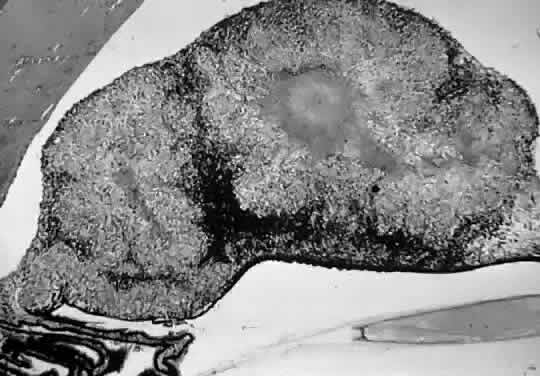

Skin biopsies from leprosy patients reveal numerous acid-fast bacilli, which may form clumps called globi. Hematoxylin and eosin staining of lepromatous skin biopsies show numerous foam cells, highly vacuolated macrophages laden with acid-fast bacilli. Skin biopsies from tuberculoid patients show few or no acid-fast bacilli, but granulomatous invasion of dermal nerves, with or without caseation, is pathognomonic. Biopsies of ocular tissues (Fig. 2) show numerous organisms inside macrophages, endothelial cells, nerves, pigment epithelium, and smooth muscle cells. There is infiltration of the conjunctiva, cornea, iris, and ciliary body with macrophages, lymphocytes, and plasma cells. Miliary lepromata are seen in iris pearls and around corneal nerves.8

Fig. 2. Light micrograph of a biopsy of an iris granuloma in a patient with leprosy. There are numerous rod-shaped bacteria consistent with M. leprae. There are multiple pigment granules with the iris stroma (Fite's stain, × 315). (Trucksis M, Baker AS: Tuberculosis and leprosy. In Albert DM, Jakobiec FA, [eds]: Principles and Practice of Ophthalmology. Philadelphia, WB Saunders, 1996.)